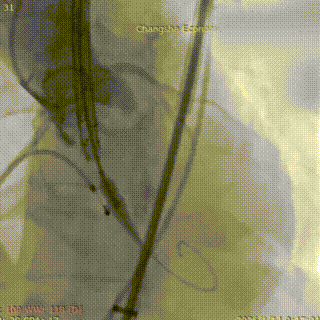

术中影像:

主动脉根部造影

患者取平卧位,在全麻及经食道超声心动图(TEE)和血管造影联合引导下,成功穿刺右侧股动脉,置入20F输送鞘管。穿刺点血管直径5.8mm,入路通畅。猪尾导管下行主动脉根部造影,清晰显示主动脉形态及无返流。在跨瓣过程中,考虑到患者心尖部心肌薄弱,导丝塑形偏大,全程操作轻柔,避免心肌损伤。